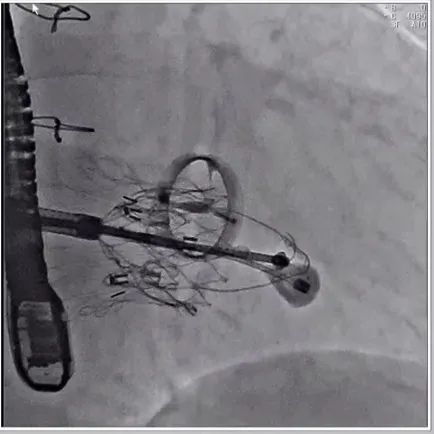

根据术前评估结果,郭应强教授团队为患者量身定制了手术策略,决定使用LuX-Valve Plus经血管三尖瓣置换系统开展手术治疗。手术在全麻下进行,采用经右侧颈静脉入路,在经食道超声和DSA的指引下调整输送器角度以达到正确位置,勾住前瓣后逐步释放盘片,盘片打开后顺利扎针,最终完成瓣膜植入,输送器撤出。术后超声提示人工三尖瓣同轴性良好,瓣架固定牢靠,无反流和瓣周漏,术后三尖瓣平均跨瓣压差为1 mmHg。

术后DSA造影